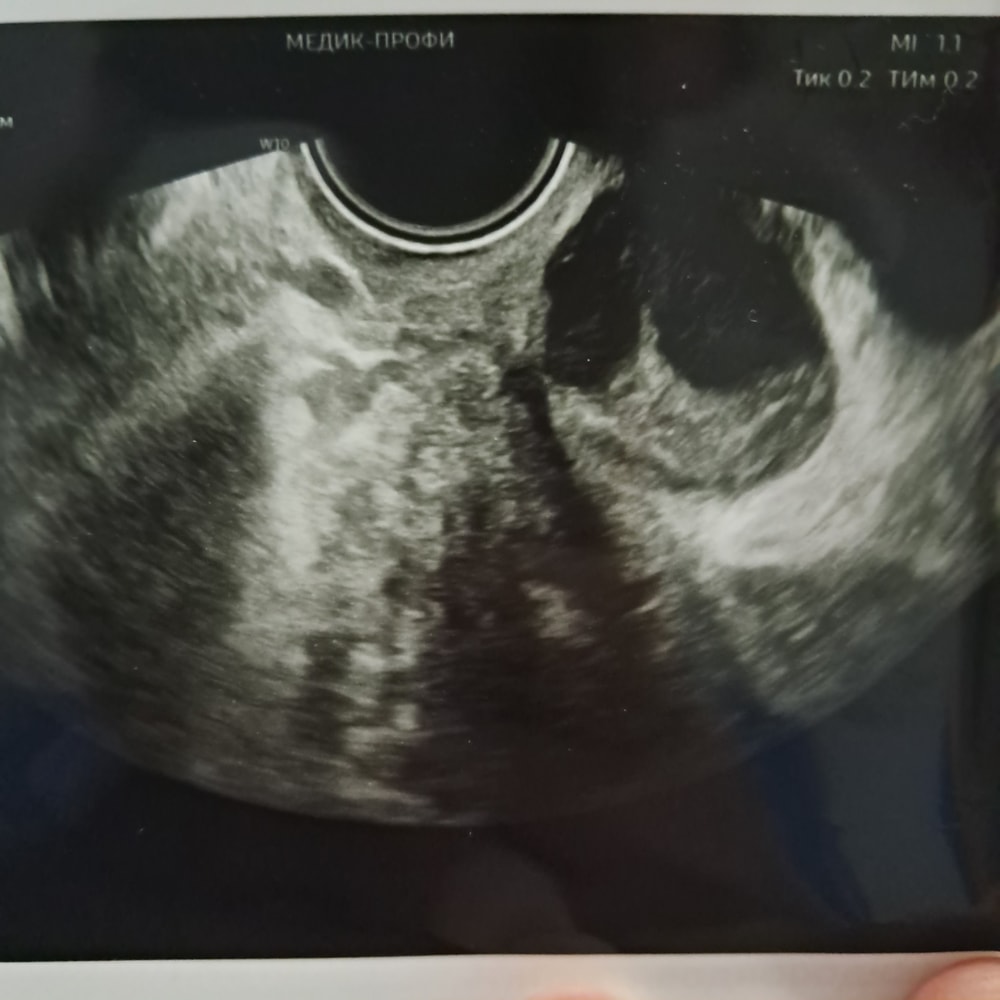

LUDMILO4KA, Изображение

12.07.2025

Лилия, фото с фото не передает картину. В энд.кисте обычно есть взвесь (на узи выглядяь как черточки внутри) У вас мес есть? Стабильно?